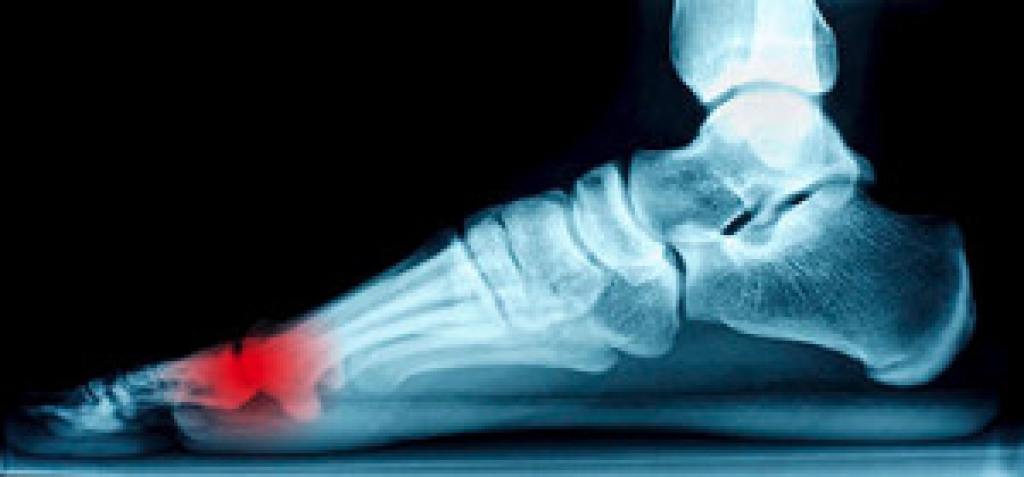

Diabetic patients can be more prone to experiencing complications with their feet. One of these complications can include a condition known as neuropathy. Neuropathy is often linked with nerve damage, which can cause a loss of feeling in the lower extremities. This can be incredibly dangerous for diabetic patients in particular, because they may be more likely to develop infections. If a diabetic patient develops a wound, however it goes unnoticed because of the neuropathy, they may be at risk of getting a foot ulcer. An ulcer is a slow healing, deep open wound that requires immediate attention. If you have diabetes, it is strongly suggested you are under the care of a podiatrist, especially if you have neuropathy.

Those with diabetes are at serious risk due to being unable to feel an ulcer on their feet. Diabetics usually also suffer from poor blood circulation. This can lead to the wound not healing, infections occurring, and the limb may have to be amputated.